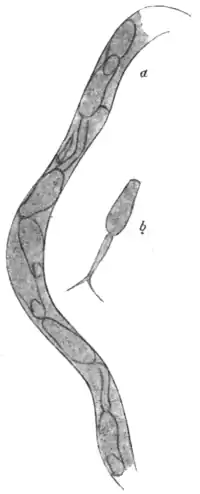

Fig. 129.—Schistosomum hæmatobium, male and female. (Partly after Looss.)

Etiology.—Schistosomum hæmatobium (Figs. 129, 130, 131) is a bisexual trematode belonging to the family Schistosomidæ. The male is white, cylindroid, 11 to 15 mm. in length by 1 mm. in breadth. It possesses an oral and a ventral sucker of about equal size and placed close together. The cylindrical appearance of the worm is produced by the ventral infolding of the two sides of what would otherwise be a flat body. By this infolding a gynæcophoric canal is formed, in which the female can be partially enclosed. The outer surface of the body is closely beset with small cuticular prominences. The female is rather darker in colour than the male, considerably longer (20 mm.), more filiform, her middle being usually enclosed in the gynæcophoric canal referred to, whilst her anterior and posterior portions remain free. The genital openings of the sexes face each other, and are placed immediately posterior to the ventral sucker. The sexes live apart while young, but on reaching maturity the female enters the gynæcophoric canal of the male.

These parasites are found in the blood of the portal vein, in its mesenteric and splenic branches, and in the vesical, uterine, and hæmorrhoidal veins; they have also been found in the vena cava. Sonsino considers that, if searched for, they would probably be found elsewhere in the circulation. Their numbers vary considerably. Sonsino reports finding in one case forty; in another case Kartulis found 300 in the portal vein and its branches. Looss has seen the submucous tissue of the bladder so rich in worms that a pair could be found in every area of half a centimetre square.